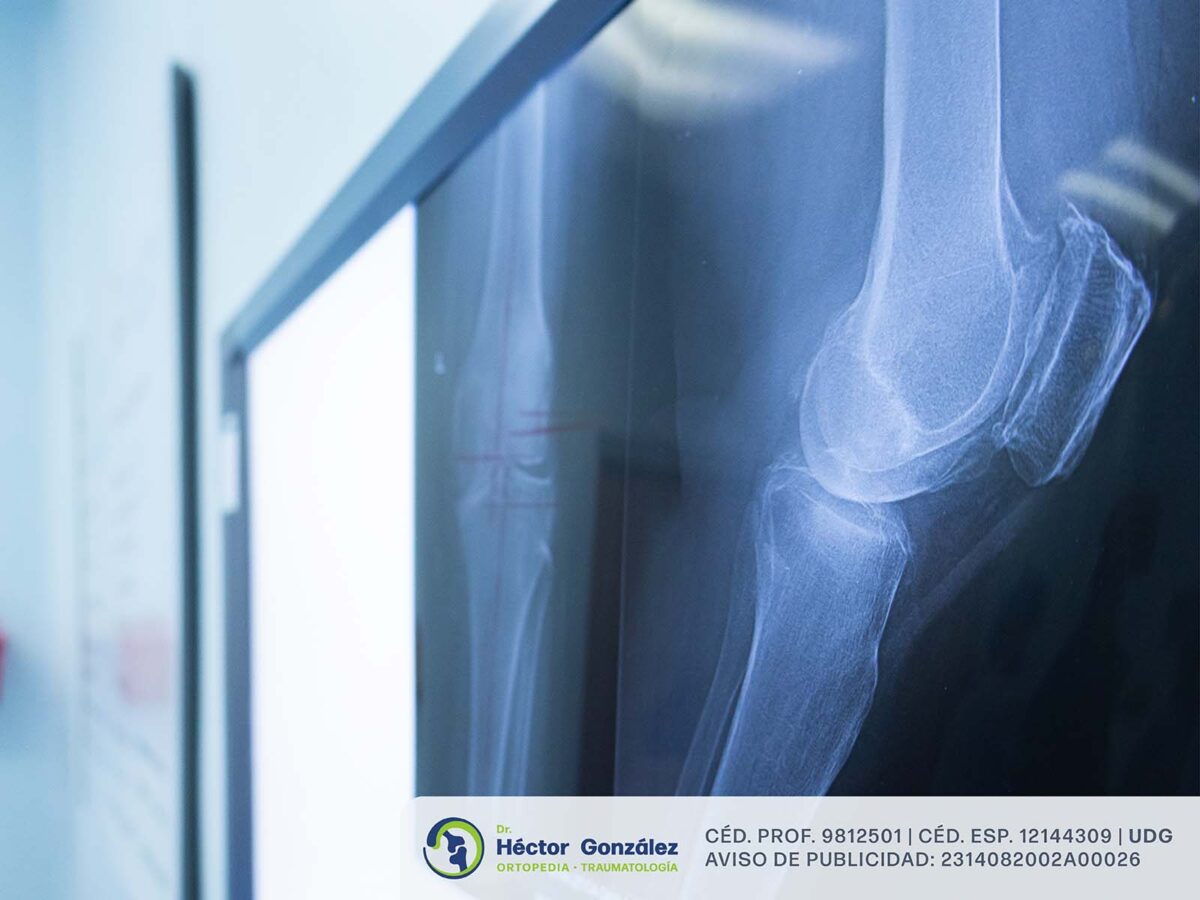

Lo primero será acudir con un especialista, como un ortopedista y traumatólogo, quien realizará una exploración física, conocerá el historial clínico y, con ayuda de estudios de imagen como radiografías, podrá determinar el mejor tratamiento.

La artroplastia de rodilla consiste en la reconstrucción de la articulación mediante una prótesis metálica.